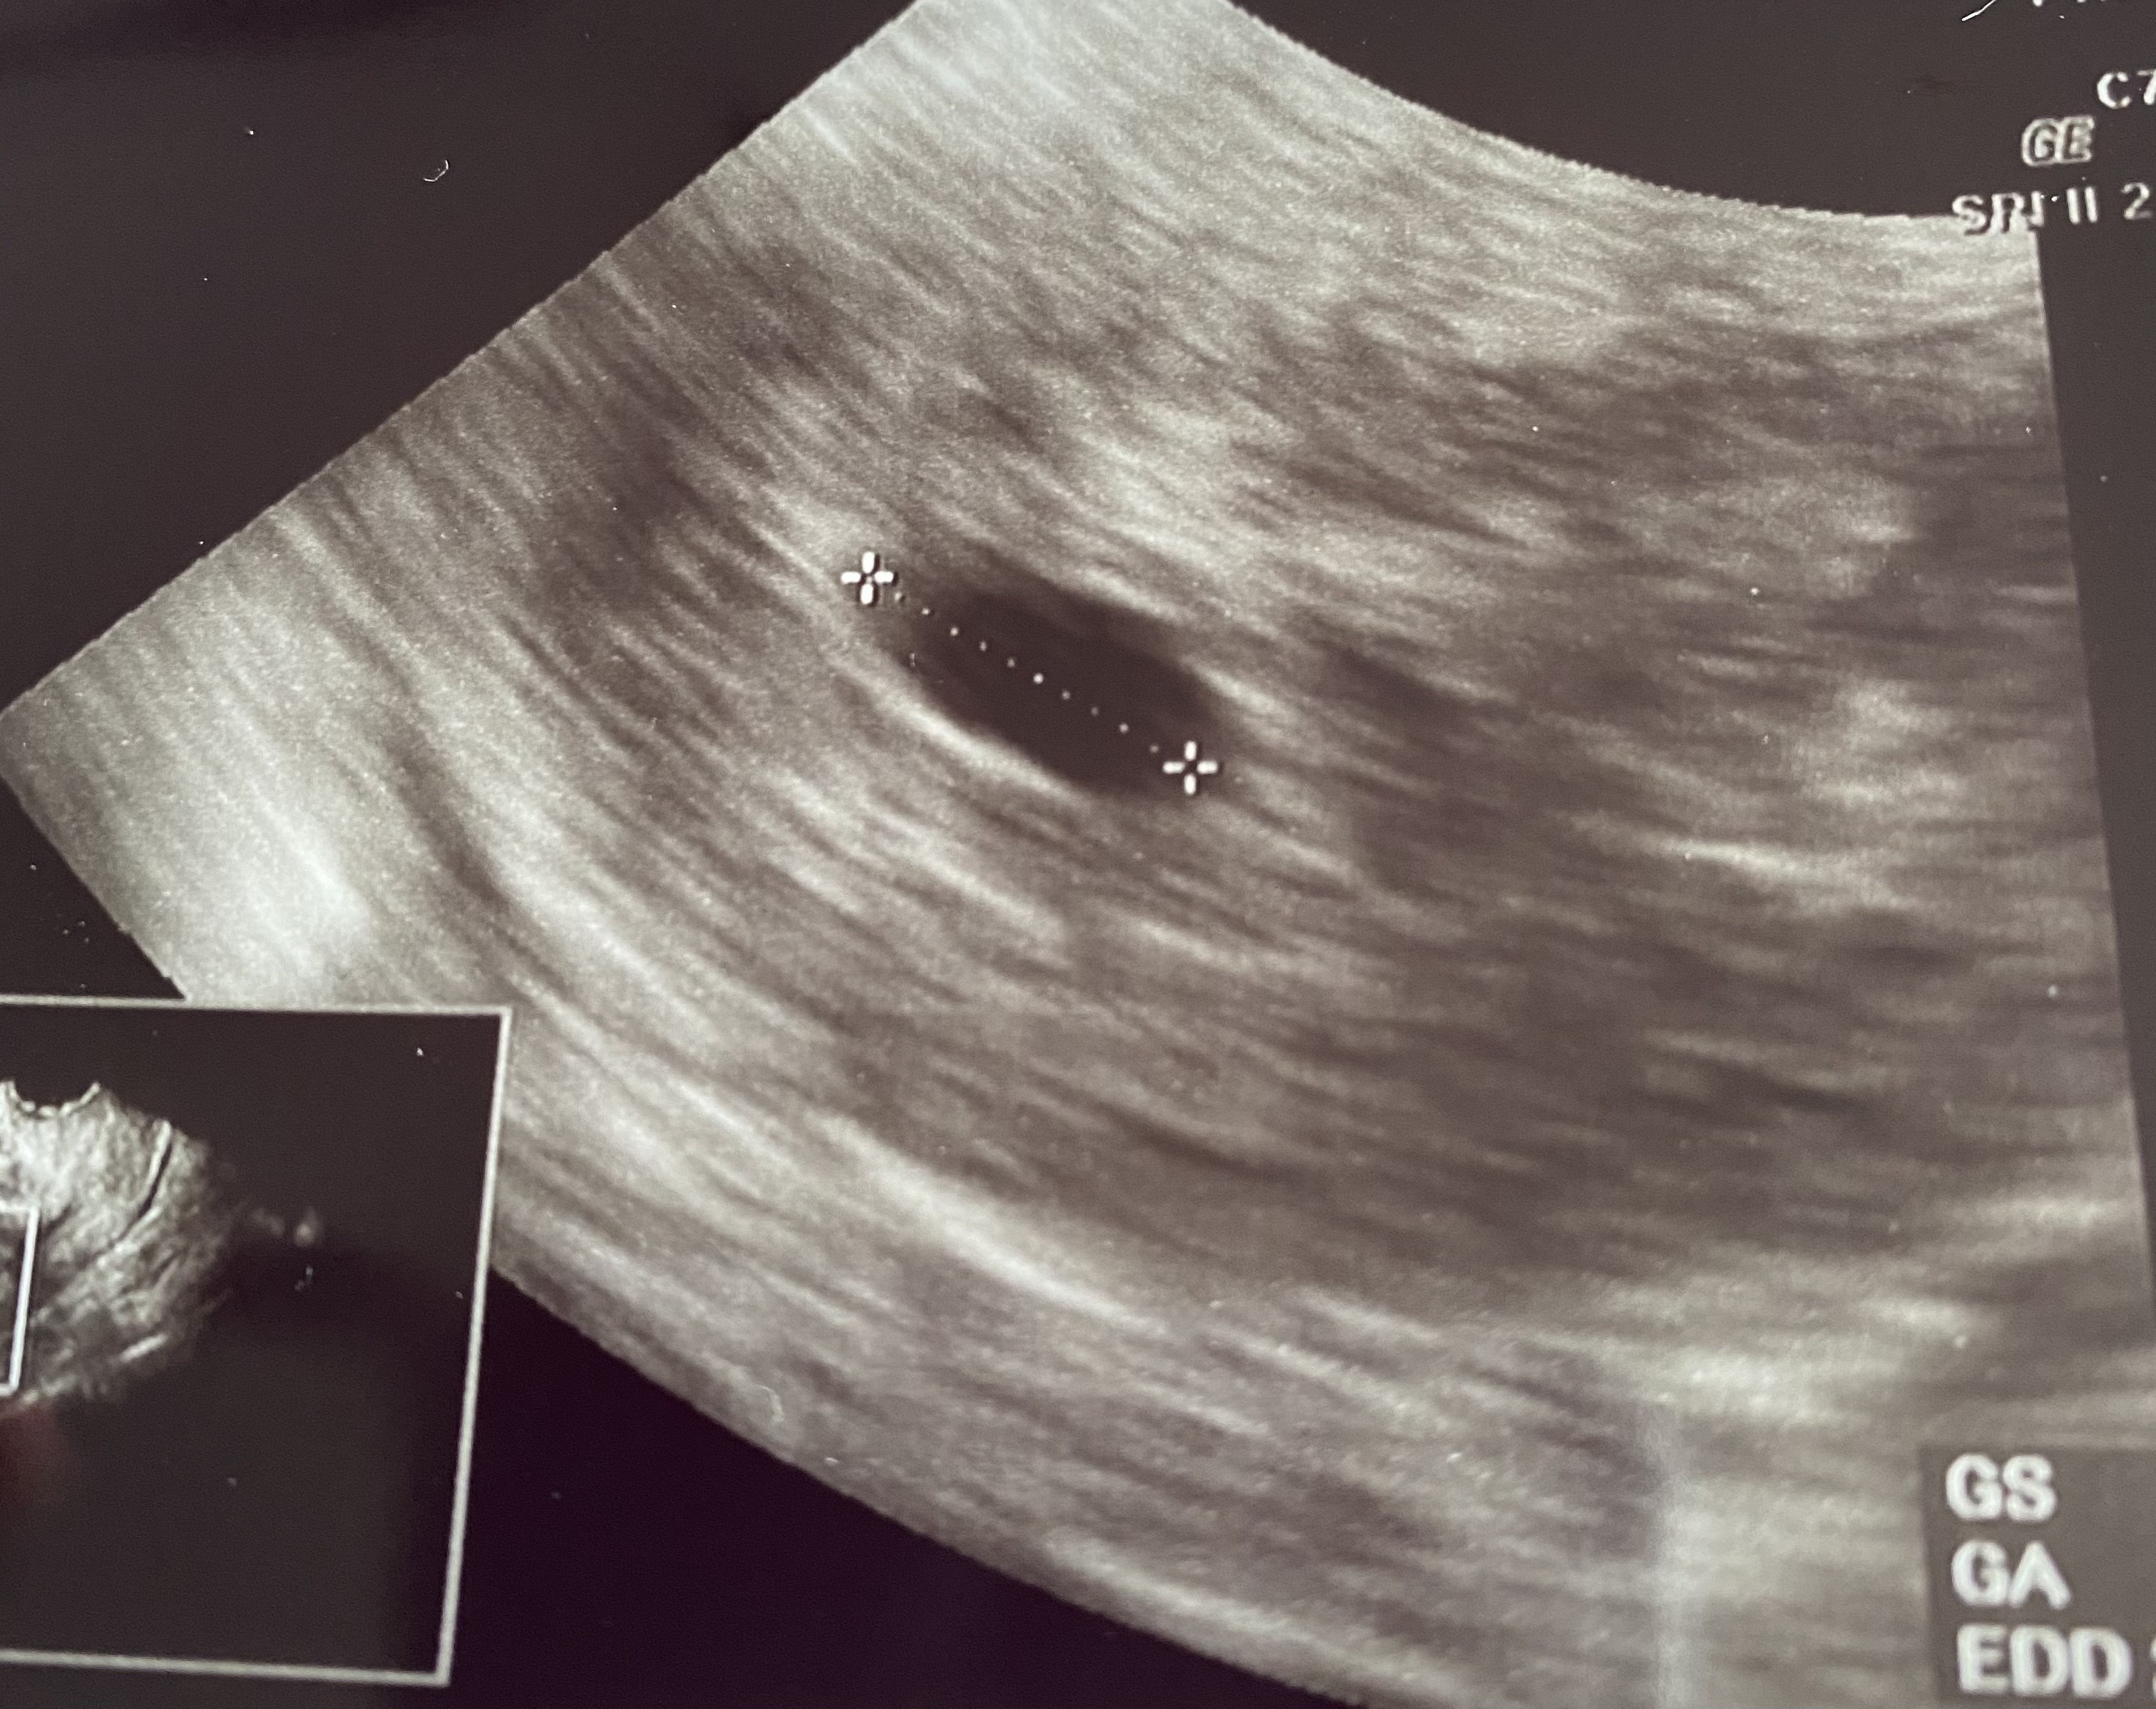

Ja miałam taki i zastanawia mnie tylko dlaczeho on zmierzył troszkę dalej już czarny obszar ?To ta kropeczka w pęcherzyku ☺

u mnie z ostatniej om 6t 5d byl i tylko pecherzyk ciążowy nic więcej nawet nic nie wytłumaczyła szok dla mnieja też wczoraj miałam właśnie

z moich obliczeń owulacja mi się przesunela 5 lub 6 dni ale to juz więcej powinno być widać chyba masakrau mnie z ostatniej om 6t 5d byl i tylko pecherzyk ciążowy nic więcej nawet nic nie wytłumaczyła szok dla mnie